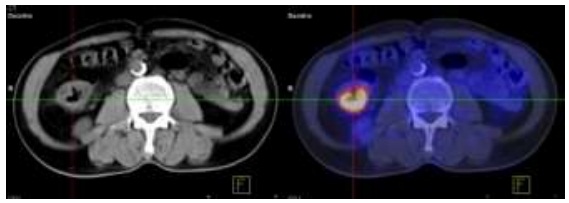

Hình ảnh PET/CT so sánh trước và sau 6 chu kỳ hóa trị:

Hình 2.6. Trước điều trị: U gan HPT VII KT: 3x4cm, SUV=7,4.

Hình 2.7. U gan phải sau hóa trị kích thước: 2x3cm, SUV=4,1.

Như vậy sau 6 chu kỳ hóa trị kết hợp Bevacizumab: Các tổn thương u nguyên phát, di căn hạch ổ bụng, nốt di căn phổi đã không còn, chất chỉ điểm khối u CA 19-9 giảm. Tuy nhiên tổn thương di căn gan vẫn tồn tại và kích thước tổn thương gan đã thuyên giảm còn 2x3cm.

Tóm lại: Bệnh đáp ứng một phần.